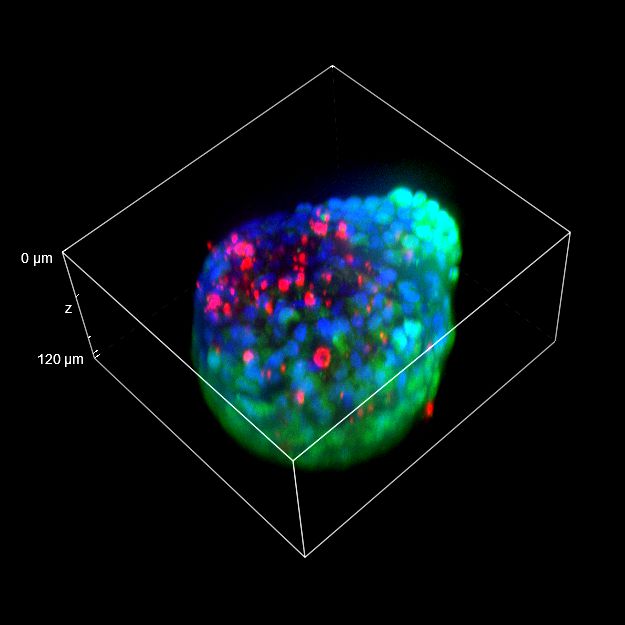

为了更好地理解 3D 细胞组织,在图 C 中,我们展示了使用两种物镜获得的同一球体的体积视图(120 um 厚),甚至在 3D 肿瘤球体的更深区域也能看到染色。最后,在 图 D 中,显示了使用 25 倍硅油物镜获得的整个球体的 3D 电影特效。

使用 20 倍空气物镜和使用 25 倍硅油物镜获得的图像之间的比较(图 A、B 和 C)突出了基于生物应用的透镜选择的重要性。从 20 倍到 25 倍的转换导致分辨率提高(基于 25 倍的 NA 大于 20 倍 NA),这当然会影响图像质量,并且还会导致光折射减少。事实上,浸油通过用更高折射率的介质代替透镜和盖玻片之间的空气间隙,大大提高了显微镜的分辨率,从而减少了光的折射。

在 3D 成像中,样品的折射率与其浸没介质的折射率相匹配对于深层组织观察至关重要。硅酮浸油非常适合透过厚厚的生物样本进行成像;它与细胞和封固剂的折射率非常吻合,与使用普通 20 倍空气物镜获得的图像相比,减少了球面像差,产生了更亮、分辨率更高的图像。

图 C:使用 20 倍空气物镜(左)和 25 倍硅油物镜(右)获得的球体的 3D 体积视图。活细胞用钙黄绿素(绿色)标记,死细胞用 PI(红色)标记。细胞核用 Hoechst(蓝色)染色。沿 Z 轴的比例尺:120 um。这些图像是使用 CrestOptics X-Light V3 转盘获取的。